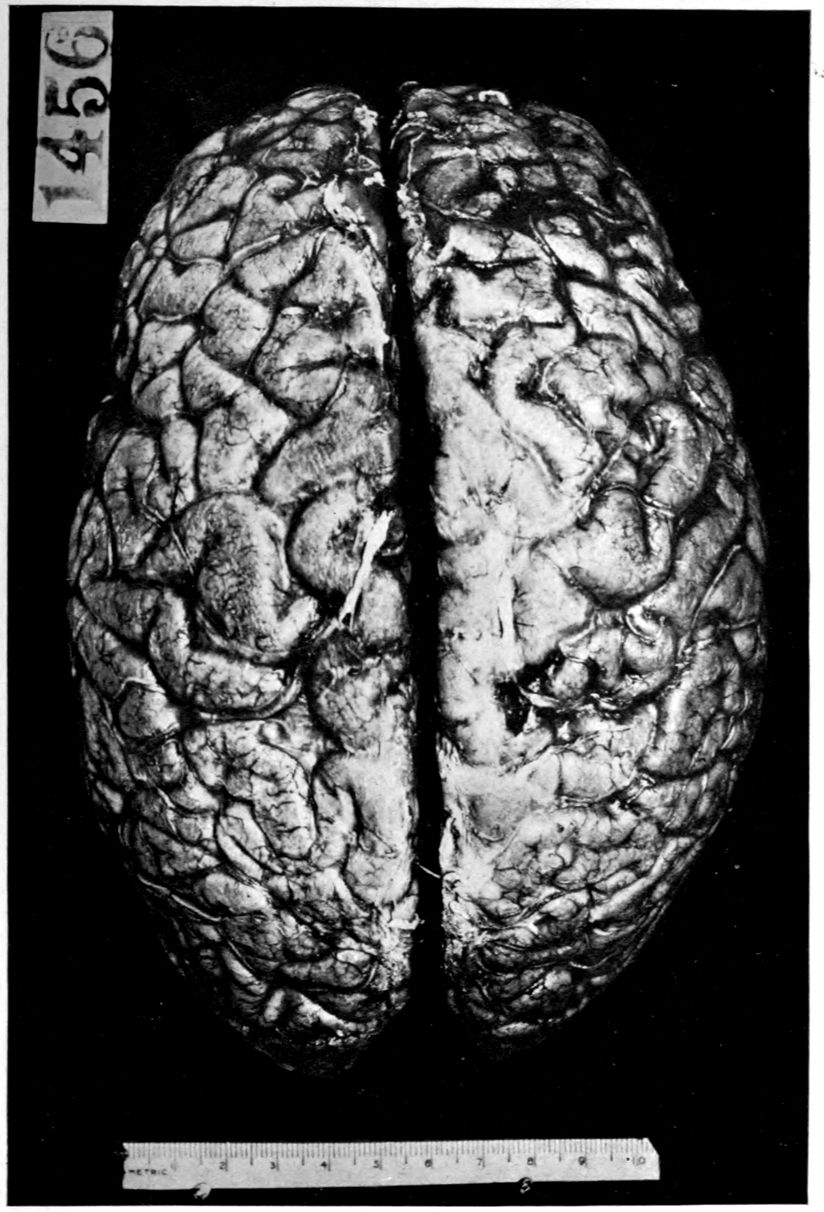

Case 4. James Pierce was an almshouse transfer to the Danvers Hospital in his fiftieth year. He died three years later. The accompanying brain pictures demonstrate so extensive a lesion of the left hemisphere that it is of great interest to determine if possible the genesis and course of his disease. It appears that syphilis had been acquired somewhere about the age of 38 or 40, so that the total duration of the process was between 13 and 15 years. In Pierce’s forty-third or forty-fourth year, he had a shock while walking in the streets of his native city, whereupon he was subsequently transferred to the Danvers Hospital, whose data have been summed up as follows (we are obliged to Dr. Charles T. Ryder for these data):

Vascular neurosyphilis—effects of syphilitic thrombosis of Sylvian artery 10 years before death. (Case 4.)